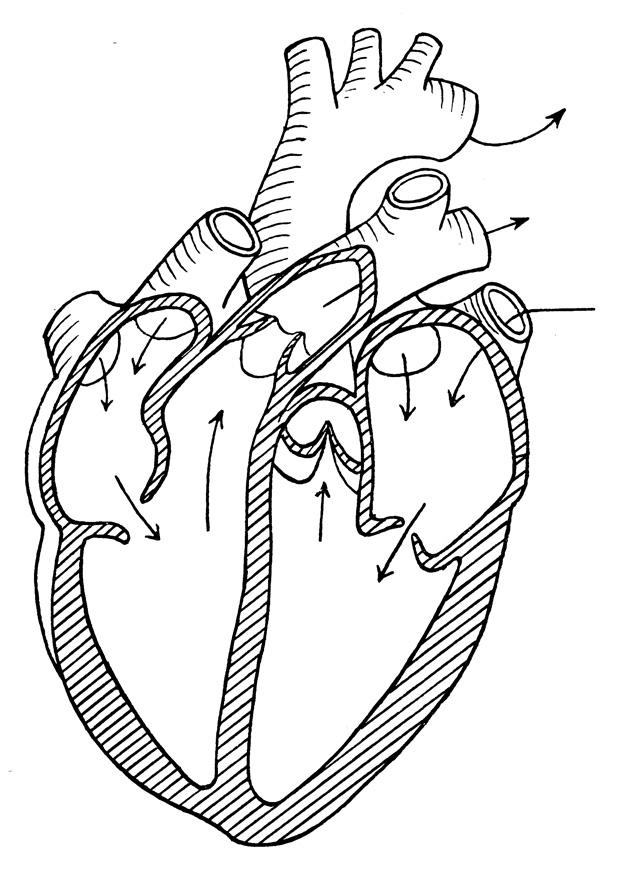

Human Heart Labeled Heart Diagram Human Heart Diagram Heart Blood Flow

Human Heart Biology